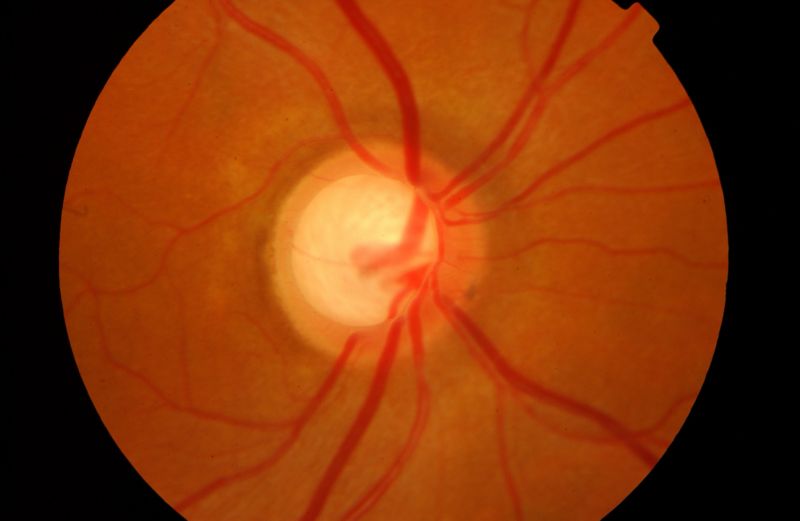

It is a group of more than 60 pathologies that affect the optic nerve and, if not treated in time, can lead to irreversible blindness.

Glaucoma is one of the main causes of blindness in people over 60 years of age, although it can manifest itself at any age. It is a group of eye diseases that cause progressive damage to the optic nerve, which is responsible for transmitting visual information to the brain.